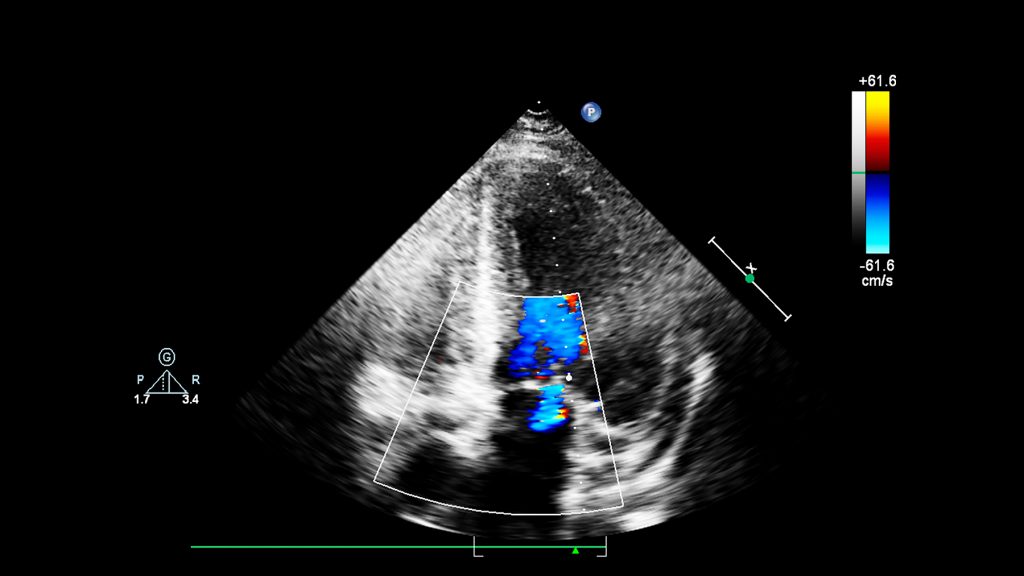

Genito-Thyroid: Chronic heart failure